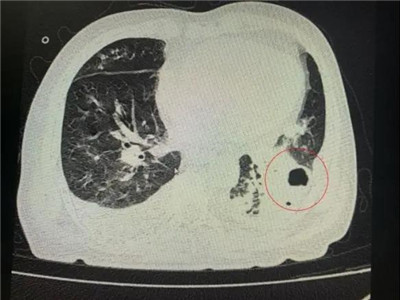

番禺院区呼吸内科何梦璋主任接诊后,对钟叔进行详细检查。此时,钟叔的病情已经十分危急,由于不能自主呼吸,他带上了无创呼吸机辅助呼吸治疗。看到钟叔胸片时,医护人员头皮也一阵发麻,胸部CT可见双肺多发的炎症浸润、双肺多发空洞。通俗来说,钟叔的肺部已经被病原体蚕食,啃出无数个大小各异的洞!可怕的是,这种病变对肺功能的破坏是永久性、不可恢复的。根据钟叔病史以及胸部CT结果,最终诊断为“吸入性肺脓肿”。

钟叔的肺部被病原体蚕食,啃出无数个大小各异的洞。